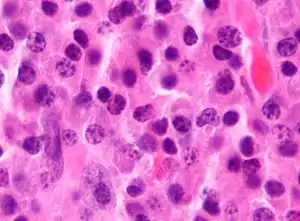

Micrograph of malignant plasma cells (plasmacytoma), many displaying characteristic "clockface nuclei", also seen in normal plasma cells. H&E stain. | |

Plasmacytoma, multiple myeloma, Waldenström macroglobulinemia and plasma cell leukemia are malignant neoplasms ("cancer") of the plasma cells.[13] Multiple myeloma is frequently identified because malignant plasma cells continue producing an antibody, which can be detected as a paraprotein.